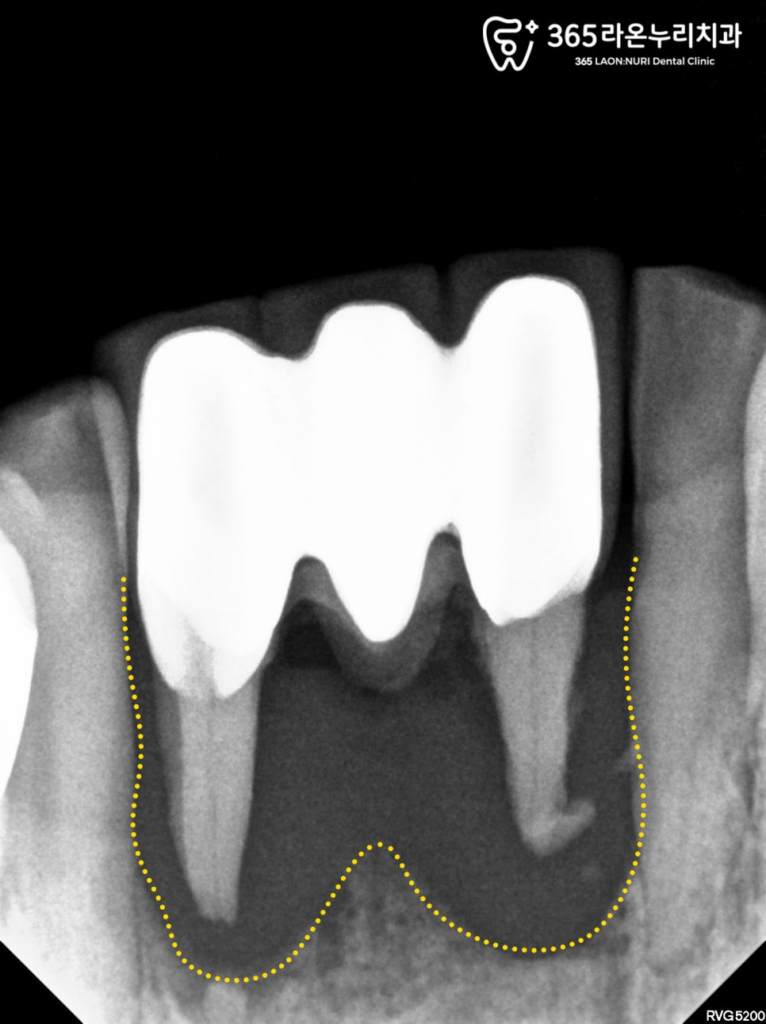

눈으로도 심한 아랫니 흔들림이 관찰되며,

동요도 검사에서도 높은 흔들림으로

mob(+++) 확인됩니다.

실제로 만졌을 때,

자연 발치가 이루어질 정도로

앞 뒤로 심하게 흔들리고 있었습니다.

치근단 사진에서도 심한 골흡수 양상이 나타나,

빠른 발치가 필요하다고 판단하게 되었습니다.